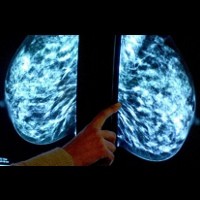

"Jika ditemukan adanya gangguan atau masalah pada payudara, maka sebaiknya segera periksakan ke dokter. Biasanya dokter akan melakukan pemeriksaan lebih lanjut berupa USG payudara, jika hasilnya masih meragukan maka akan dilanjutkan dengan mamografi untuk mengetahui apakah tumor jinak atau ganas," ungkapnya.